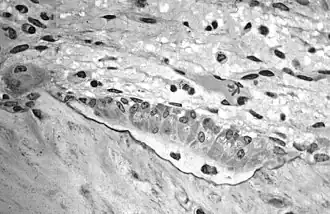

![]() Osteoblasts (purple) rimming a bony spicule (pink - on diagonal of image). In this routinely fixed and decalcified (bone mineral removed) tissue, the osteoblasts have retracted and are separated from each other and from their underlying matrix. In living bone, the cells are linked by tight junctions and gap junctions, and integrated with underlying osteocytes and matrix H&E stain. | |

Hematoxylin and eosin staining (H&E) shows that the cytoplasm of active osteoblasts is slightly basophilic due to the substantial presence of rough endoplasmic reticulum. The active osteoblast produces substantial collagen type I. About 10% of the bone matrix is collagen with the balance mineral.[29] The osteoblast's nucleus is spherical and large. An active osteoblast is characterized morphologically by a prominent Golgi apparatus that appears histologically as a clear zone adjacent to the nucleus. The products of the cell are mostly for transport into the osteoid, the non-mineralized matrix. Active osteoblasts can be labeled by antibodies to Type-I collagen, or using naphthol phosphate and the diazonium dye fast blue to demonstrate alkaline phosphatase enzyme activity directly.